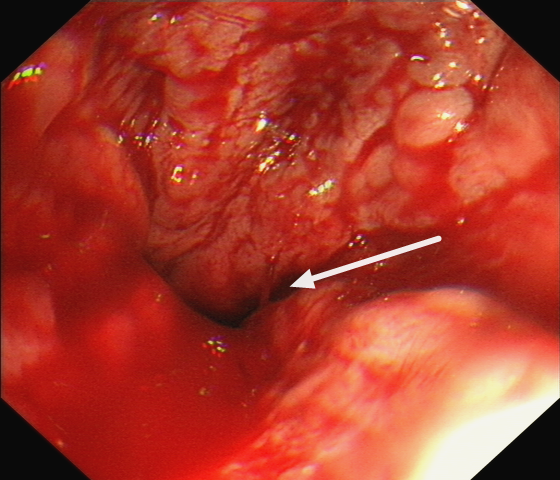

胃鏡下可見明顯“血柱”

醫(yī)生立即決定完善急診胃鏡檢查,患者內(nèi)鏡下食管靜脈曲張如藤蔓一般盤根錯節(jié),可見一處“血柱”像噴泉一樣源源不斷涌出,此時內(nèi)科藥物治療已難以達(dá)到止血目的。

術(shù)后胃鏡圖片